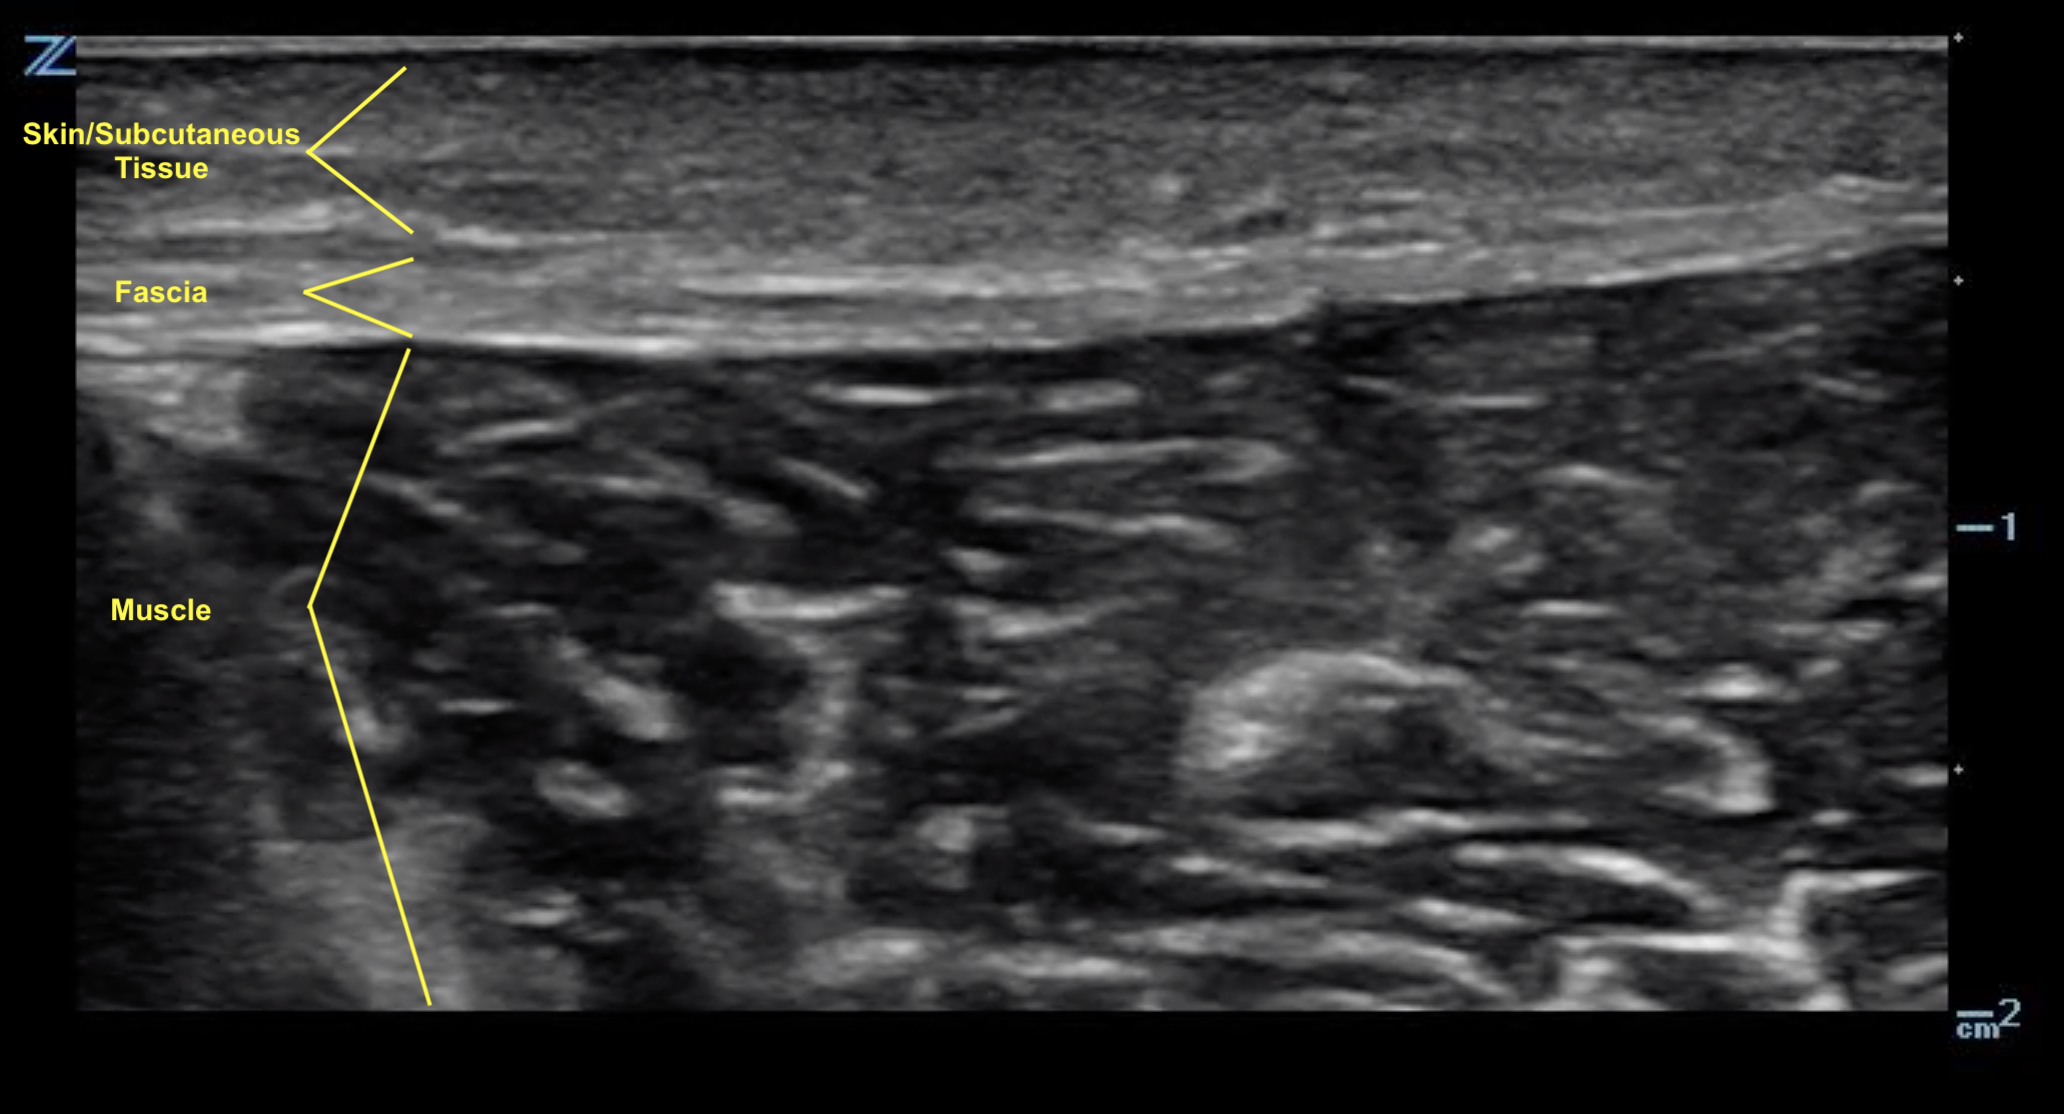

Ultrasound anatomy of the abdominal wall layers. EOM, external oblique Layers Of Skin On Ultrasound The most superficial layer of the skin is the epidermis, which contains keratinocytes, melanocytes, and langerhans cells. This chapter reviews the normal sonographic anatomy of the skin, hair, nail, and relevant adjacent structures, with emphasis on the key ultrasound points. The spatial resolution of us nowadays allows optimal definition of the skin layers, similar to histologic sections, according. Layers Of Skin On Ultrasound.

Ultrasound Leadership Academy Intro to Musculoskeletal Ultrasound — EM Layers Of Skin On Ultrasound The spatial resolution of us nowadays allows optimal definition of the skin layers, similar to histologic sections, according. The most superficial layer of the skin is the epidermis, which contains keratinocytes, melanocytes, and langerhans cells. This chapter reviews the normal sonographic anatomy of the skin, hair, nail, and relevant adjacent structures, with emphasis on the key ultrasound points. Layers Of Skin On Ultrasound.